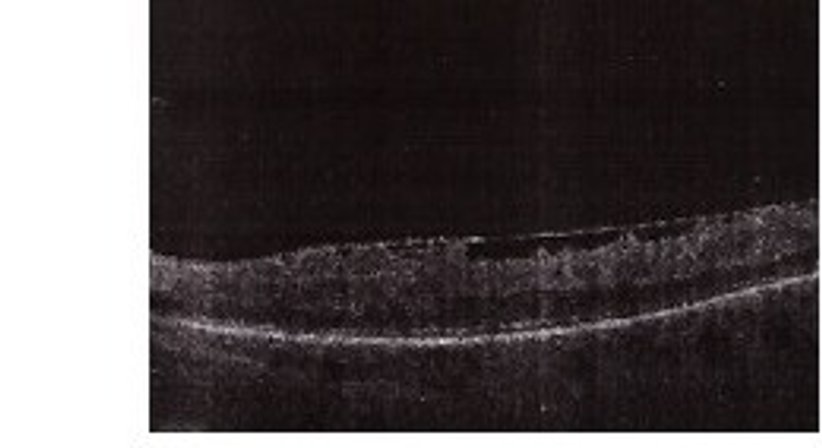

Bei manchen Erkrankungen (zB. Diabetes mellitus, erhöter Blutdruck, ...) aber auch im Alter, können Veränderungen auf der Netzhaut auftreten die eine Therapie erfordern:

• Netzhautschwellungen

• Netzhautablösungen

• Epiretinale Membranen

• Makulaforamen